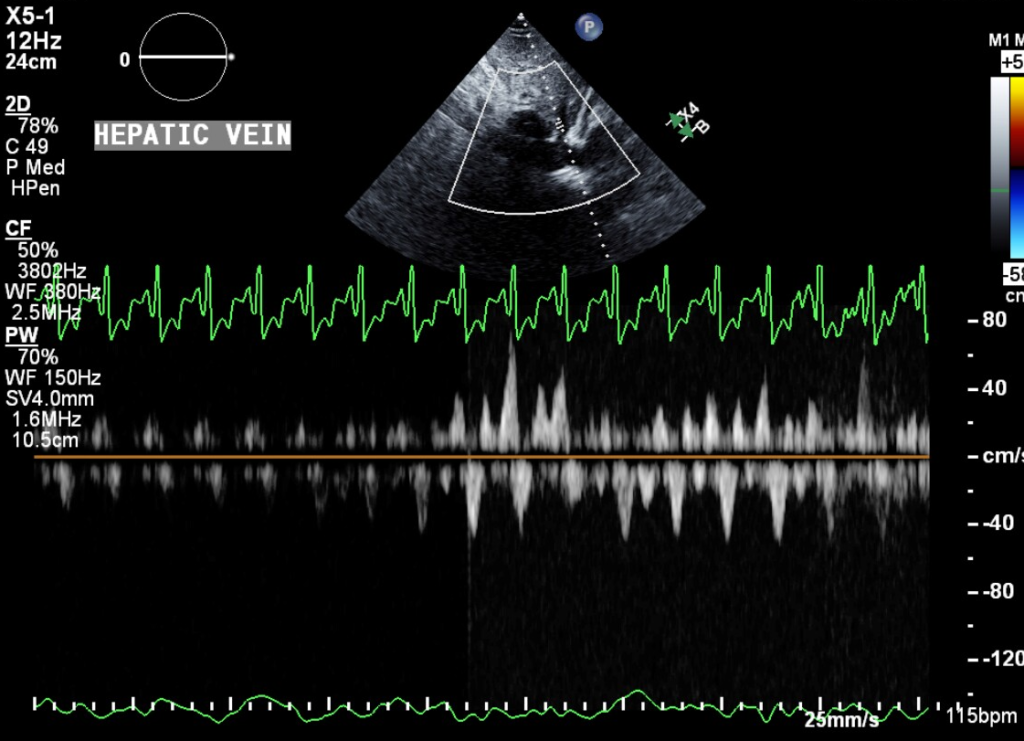

Abnormal hepatic vein venous flow refers to inspiratory systolic predominance of hepatic vein forward flow, expiratory reduction of hepatic vein forward flow, or reversal of hepatic vein flow during diastole. During apnea, forward flow in the hepatic vein only occurs during ventricular systole, not diastole. During inspiration, systolic flow becomes exaggerated, and diastolic flow appears. Systolic flow is reduced to baseline during expiration, and diastolic flow becomes reversed. The reversal of hepatic vein diastolic flow occurs exactly when the tricuspid inflow is lowest.